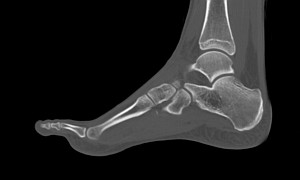

Стопа